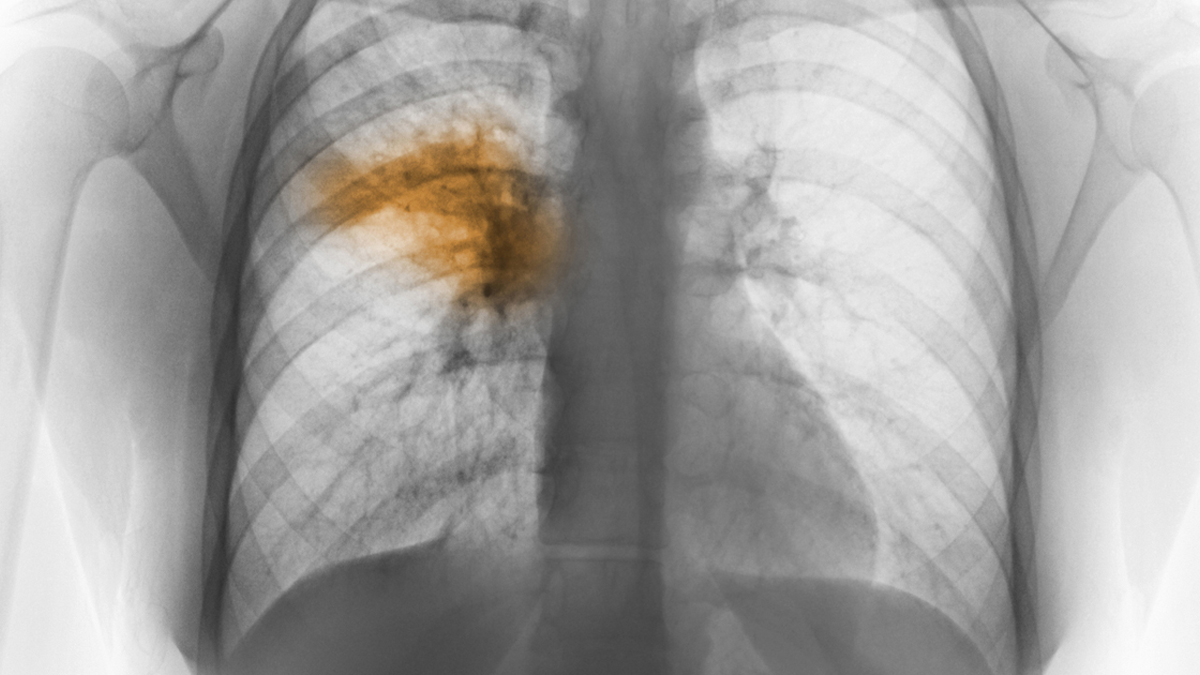

AT least 155 people died of pneumonia and other respiratory diseases in just one week from 11 to 18 January 2021, Home Affairs Minister Motlalentoa Letsosa has said.

Mr Letsosa said the figures reflected a sharp increase from just 11 deaths from pneumonia and other respiratory diseases in January 2020.

Mr Letsosa said they found that whereas there had only been eight pneumonia related deaths in 2020, the figure had risen sharply to 97 deaths in just one week from 11 to 18 January 2021.

He said deaths whereas there were only three deaths from other respiratory illnesses in January 2020, the figure stood at 58 from 11 to 18 January 2021.

Many people believe the spike in respiratory and pneumonia related deaths could be in fact be Covid-19 deaths which have not been reported as such as the deceased would not have been tested for the virus.